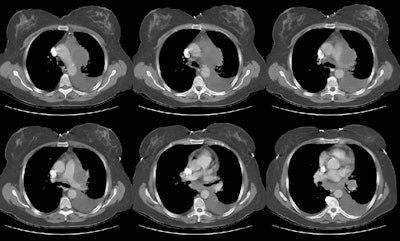

The patient below was a 57 year old female who presented with complaints of weight loss. A chest radiograph demonstrated an aortopulmonary window mass (best seen on the PA chest radiograph) and a left sided pleural effusion. (Click here if you would like to view the lateral chest radiograph). A CT scan of the chest was performed to evaluate this finding.

The chest CT demonstrated a large, low density mass in the aortopulmonary window, as well as the presence of subcarinal and left hilar adenopathy. There is a large left sided pleural effusion. At surgery the patient was found to have a Non-Hodgkins B-cell lymphoma.